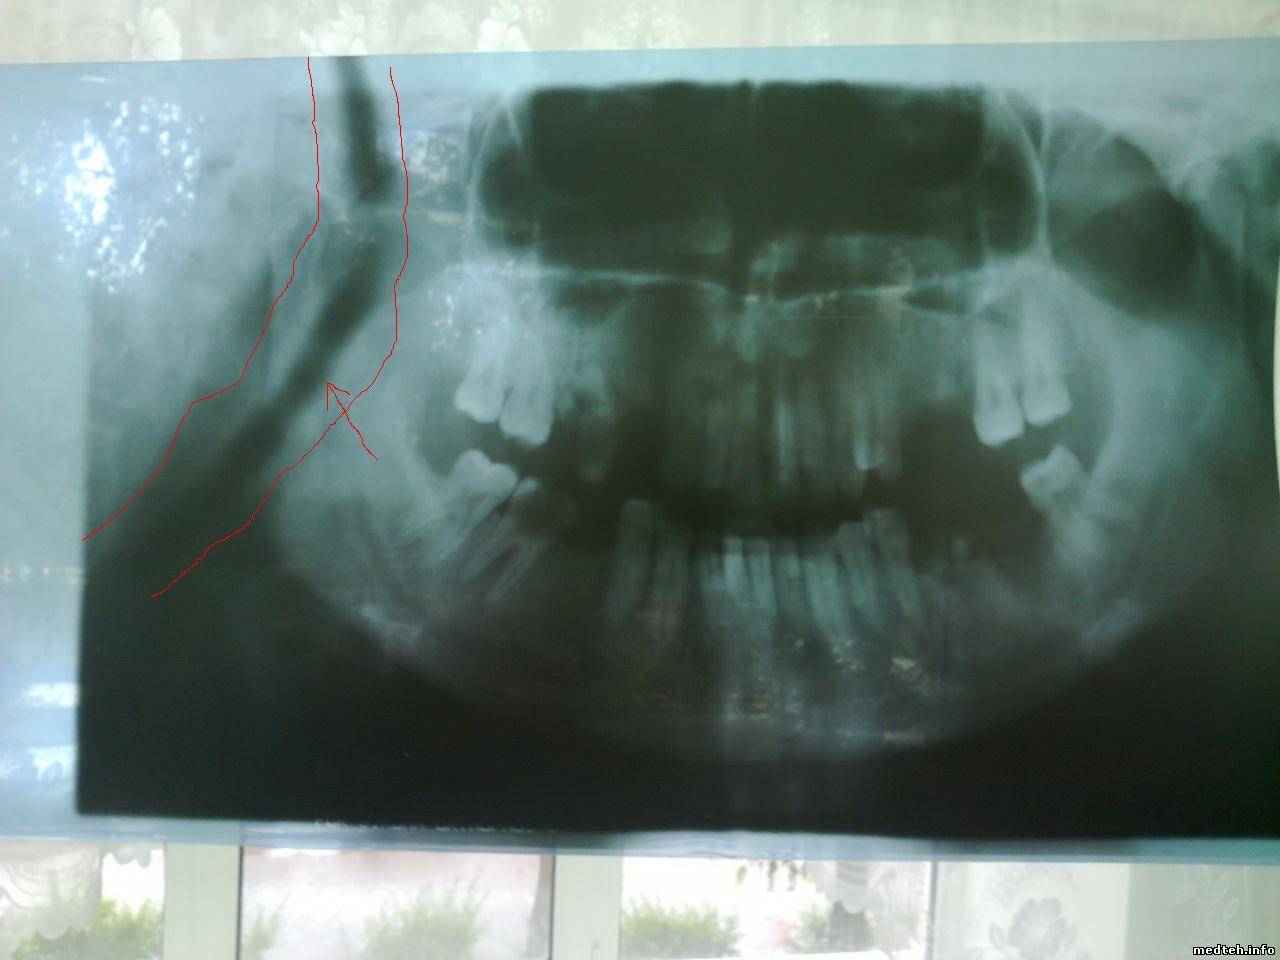

если не совсем понятно, еще могу найти снимки. это на первой программе сделано.

1279257.jpg (67.0 Kb) · 7272345.jpg (68.9 Kb)

неее, там 1 программа- обычная панорамная съемка, 11- панорамная съемка при 1,3-кратном увеличении, 6.1и 6.2-съемка суставов.

вот снимок что на фото- это 1 программа. В снимок то все входит, как на нормальном панорамном. вот почему он получается зауженным, я не понимаю. При чем с слева и справа одинаковое расстояние. время экспозиции-11 с., то есть как положено.

Интересно почему на снимках правая сторона черная (засвечена), а левая белая (нет высокого)?

Получается надо регулировать начало и конец подачи высокого.

И увеличивать скорость движения кассеты.

По поводу почернения на правой стороне мне вообще непонятно, после этого почернения следует белая"прожилка", то есть как будто выключено высокое , и снова включается когда начинается снимок. примерно 3 мм- "прожилка". хотя во время сьемки луч не выключается.